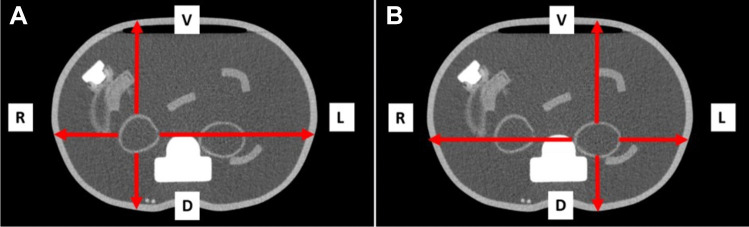

Procedures: A dedicated torso phantom with kidneys filled with a solution of 177Lu-PSMA was used for quantitative calibration of a SPECT-camera. The calculated sensitivity was adapted according to the individual attenuation of the patient in four directions from the kidney surface to the body surface (ventral, dorsal, left and right) obtained from a previously performed CT. A total of 196 patients undergoing 926 cycles of 177Lu-PSMA therapy were retrospectively analyzed. Abdominal SPECT was performed 24, 48 and 72 h after administration of 177Lu-PSMA including scatter and dead-time correction in every patient. Kidney dose was calculated using an individual attenuation-based procedure and compared to values from international literature.